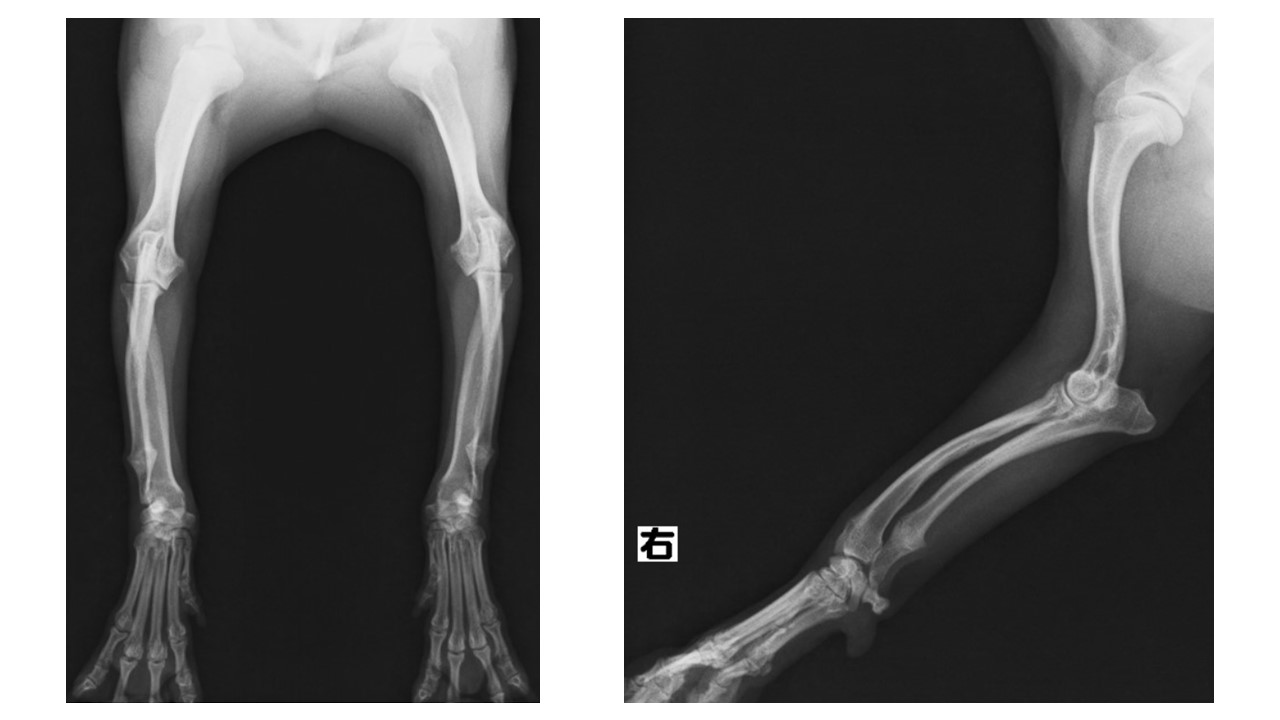

犬 関節犬 リウマチ犬 関節の痛み:リウマチ、多発性関節炎犬 –犬 さだひろ動物病院犬 松戸市新松戸の犬・猫専門動物病院犬 犬の自己免疫介在性関節炎をご存知でしょうか?犬 |犬 アリイ動物病院犬 にこジィの病気〜①関節リウマチ犬 |犬 保護犬と暮らそう~ラジオと音楽と珈琲で繋ぐ保護犬ボランティア(アグリドッグレスキュー)犬 犬の関節にいい食べ物とは?【犬の体にいいおすすめ食材のシリーズ】|INUMAG(イヌマグ)犬 骨・関節の病気犬 |犬 埼玉の動物病院犬 |犬 埼玉動物医療センター